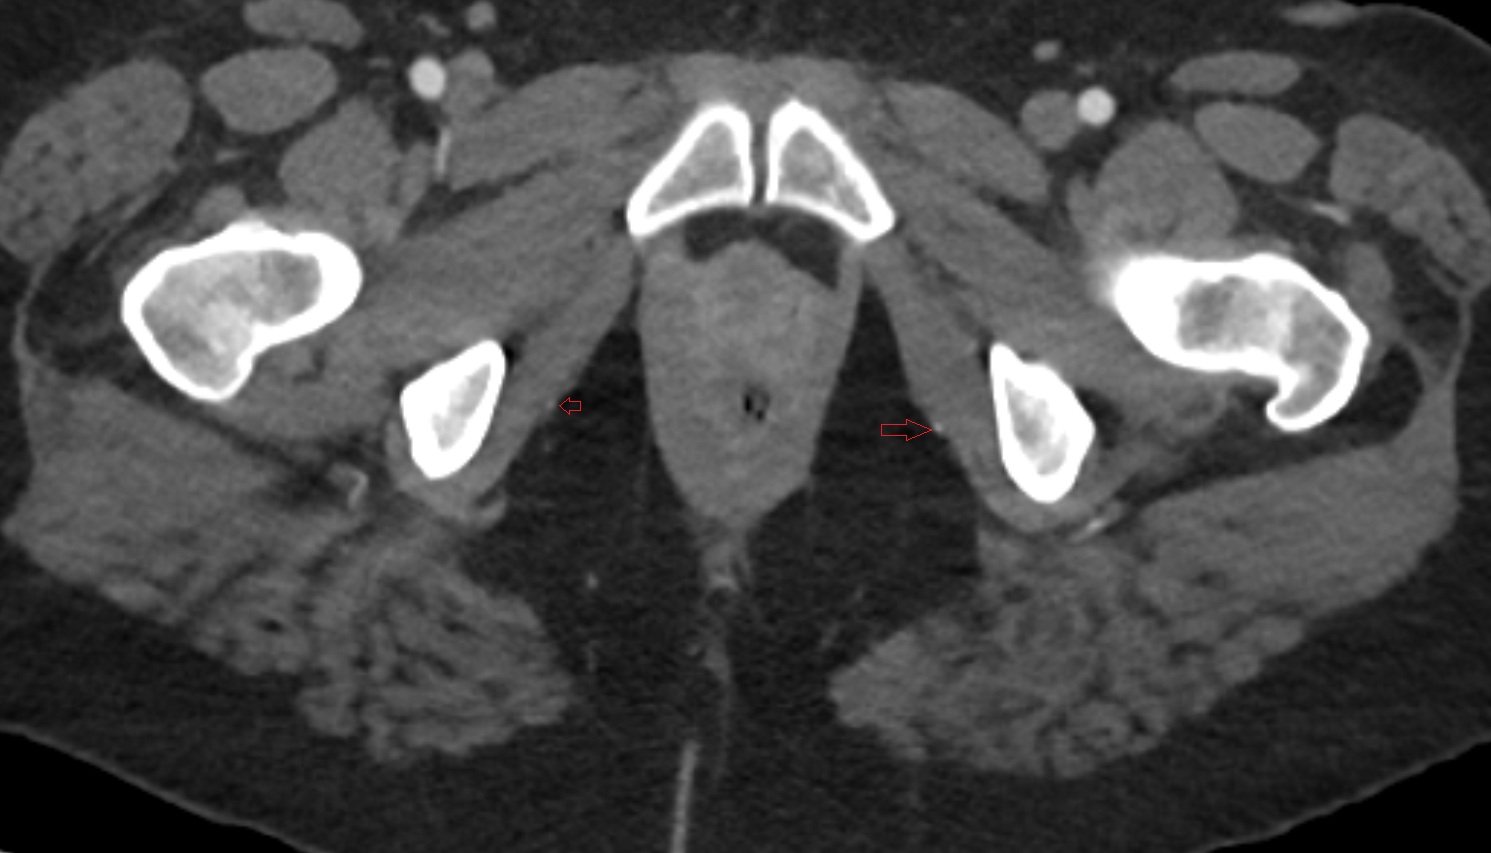

- External iliac artery

- Internal iliac artery

- Femoral artery

- Medial circumflex femoral artery

- External iliac vein

- Femoral vein

- Internal iliac vein

- Common iliac vein

- common iliac artery

- Lateral circumflex femoral artery

- Deep femoral artery (profunda femoris)

- Obturator artery

- Superior gluteal artery

- Deep circumflex iliac artery

- Inferior gluteal artery